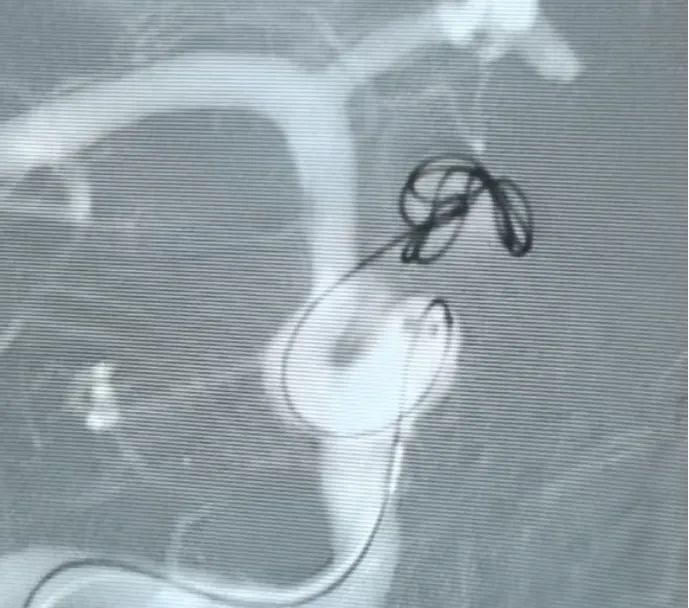

Vascular access was established via femoral artery puncture, and a Perdenser® 6 mm × 20 cm 3D coil was first deployed to form a basket, achieving stable wall apposition and providing secure intrasaccular support. This was followed by the insertion of a Perdenser® 6 mm × 15 cm 3D coil to disrupt blood flow within the lobulated daughter sac.

A Perfiller® 3 mm × 6 cm expansible coil and a Perfiller® 3 mm × 2 cm expansible coil were then placed to complete neck occlusion. Subsequently, a Nuva® Flow Diverter (TJED-D-5.0-16) was delivered and deployed across the aneurysm neck. Follow-up angiography in both anteroposterior and lateral views confirmed excellent coverage, good wall apposition, and clear radiopacity, with marked contrast stagnation.